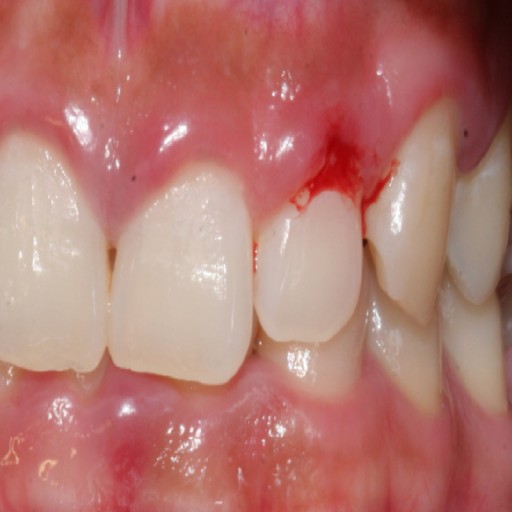

잇몸이 붓고 피가 나기 시작하면 잇몸 염증의 징후로 주의와 관리가 필요한 질환입니다. 건강한 잇몸은 치아와 지지 구조를 보호하는 장벽을 제공하면서 구강 건강의 필수적인 부분입니다.

잇몸이 붓고 피가 나는 원인

잇몸이 붓고 피가 나는 것은 구강위생 불량부터 호르몬 변화와 근본적인 건강 상태에 이르기까지 다양한 원인을 가질 수 있습니다. 잇몸 염증의 원인이 되는 일반적인 요인에는 잇몸 질환, 부적절한 구강 위생 습관, 임신이나 사춘기 동안 호르몬 변화, 영양 결핍, 특정 약물 및 스트레스가 포함됩니다.

잇몸 염증의 원인 치주 질환으로도 알려진 잇몸 질환은 잇몸 염증의 일반적인 원인입니다. 구강 내 박테리아가 잇몸선을 따라 치아 사이에 쌓이는 끈적끈적한 막인 플라크를 형성할 때 발생합니다. 정기적인 양치질과 치실을 통해 제거하지 않으면 치석이 딱딱해져 잇몸 염증이 생기고 결국 잇몸 질환이 발생합니다.